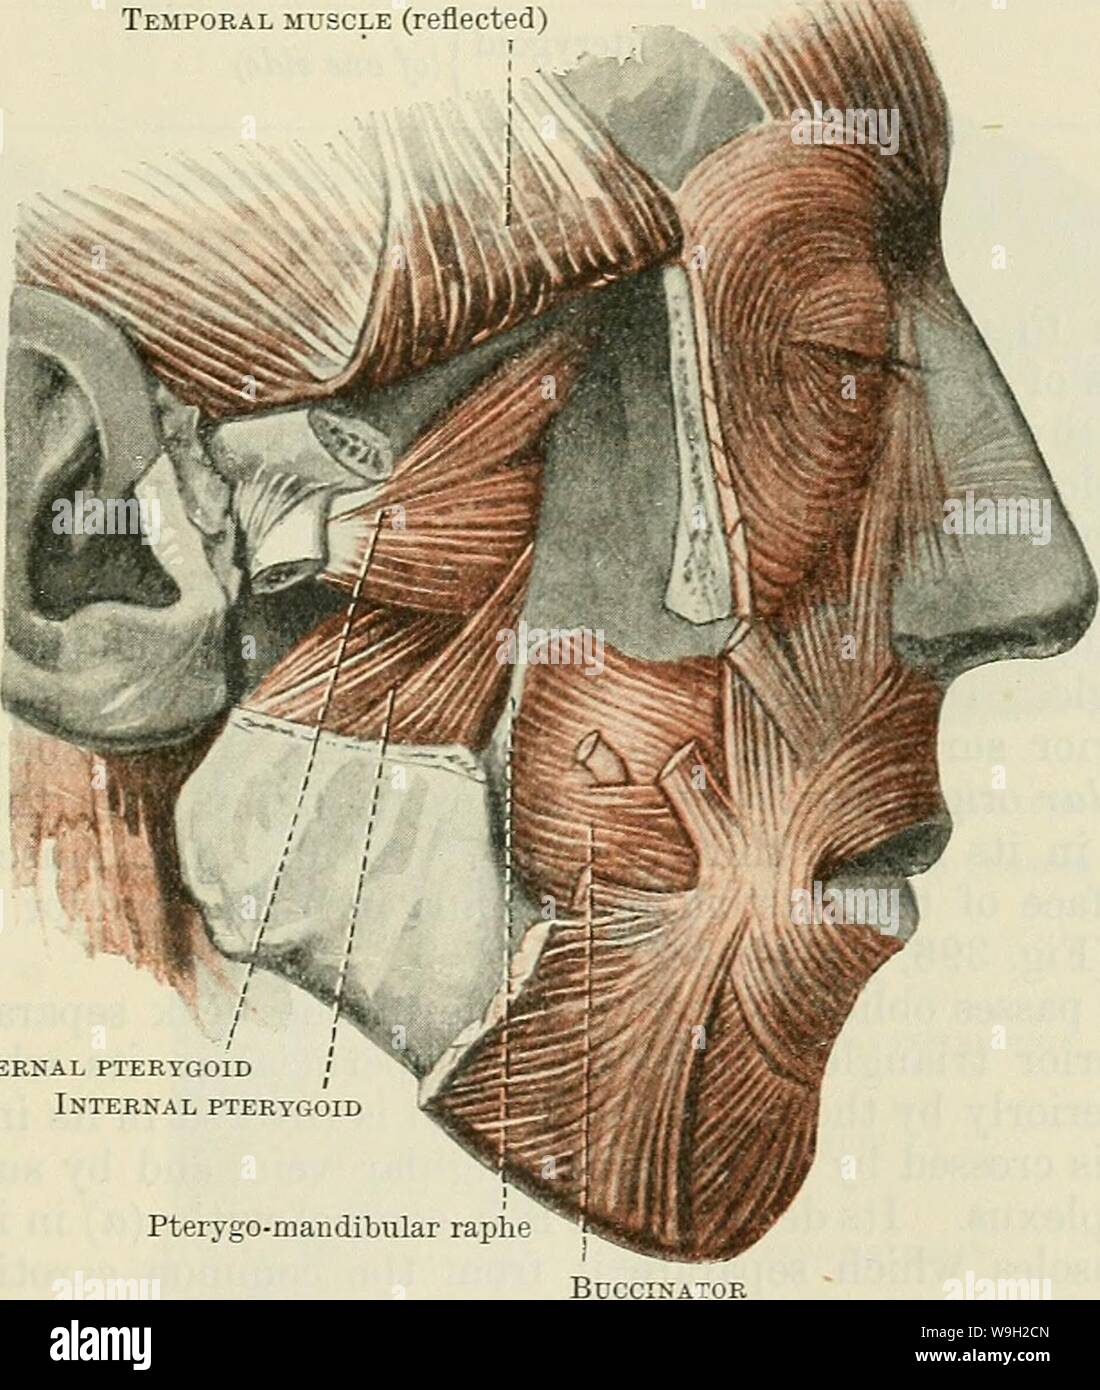

Archive image from page 490 of Cunningham's Text-book of anatomy (1914). Cunningham's Text-book of anatomy cunninghamstextb00cunn Year: 1914 ( MUSCLES OF MASTICATION. 457 fovea pterygoidea on the anterior aspect of the neck of the mandible (Figs. 403 and 404, p. 455), and (2) the articular disc and capsule of the mandibular articulation. This muscle is covered by the insertion of the temporal muscle and the coronoid process of the mandible, and is usually crossed by the internal maxillary artery. It conceals the mandibular branch of the trigeminal nerve, and the pterygoid origin of the intern Stock Photohttps://www.alamy.com/image-license-details/?v=1https://www.alamy.com/archive-image-from-page-490-of-cunninghams-text-book-of-anatomy-1914-cunninghams-text-book-of-anatomy-cunninghamstextb00cunn-year-1914-muscles-of-mastication-457-fovea-pterygoidea-on-the-anterior-aspect-of-the-neck-of-the-mandible-figs-403-and-404-p-455-and-2-the-articular-disc-and-capsule-of-the-mandibular-articulation-this-muscle-is-covered-by-the-insertion-of-the-temporal-muscle-and-the-coronoid-process-of-the-mandible-and-is-usually-crossed-by-the-internal-maxillary-artery-it-conceals-the-mandibular-branch-of-the-trigeminal-nerve-and-the-pterygoid-origin-of-the-intern-image264062533.html

Archive image from page 490 of Cunningham's Text-book of anatomy (1914). Cunningham's Text-book of anatomy cunninghamstextb00cunn Year: 1914 ( MUSCLES OF MASTICATION. 457 fovea pterygoidea on the anterior aspect of the neck of the mandible (Figs. 403 and 404, p. 455), and (2) the articular disc and capsule of the mandibular articulation. This muscle is covered by the insertion of the temporal muscle and the coronoid process of the mandible, and is usually crossed by the internal maxillary artery. It conceals the mandibular branch of the trigeminal nerve, and the pterygoid origin of the intern Stock Photohttps://www.alamy.com/image-license-details/?v=1https://www.alamy.com/archive-image-from-page-490-of-cunninghams-text-book-of-anatomy-1914-cunninghams-text-book-of-anatomy-cunninghamstextb00cunn-year-1914-muscles-of-mastication-457-fovea-pterygoidea-on-the-anterior-aspect-of-the-neck-of-the-mandible-figs-403-and-404-p-455-and-2-the-articular-disc-and-capsule-of-the-mandibular-articulation-this-muscle-is-covered-by-the-insertion-of-the-temporal-muscle-and-the-coronoid-process-of-the-mandible-and-is-usually-crossed-by-the-internal-maxillary-artery-it-conceals-the-mandibular-branch-of-the-trigeminal-nerve-and-the-pterygoid-origin-of-the-intern-image264062533.htmlRMW9H2CN–Archive image from page 490 of Cunningham's Text-book of anatomy (1914). Cunningham's Text-book of anatomy cunninghamstextb00cunn Year: 1914 ( MUSCLES OF MASTICATION. 457 fovea pterygoidea on the anterior aspect of the neck of the mandible (Figs. 403 and 404, p. 455), and (2) the articular disc and capsule of the mandibular articulation. This muscle is covered by the insertion of the temporal muscle and the coronoid process of the mandible, and is usually crossed by the internal maxillary artery. It conceals the mandibular branch of the trigeminal nerve, and the pterygoid origin of the intern